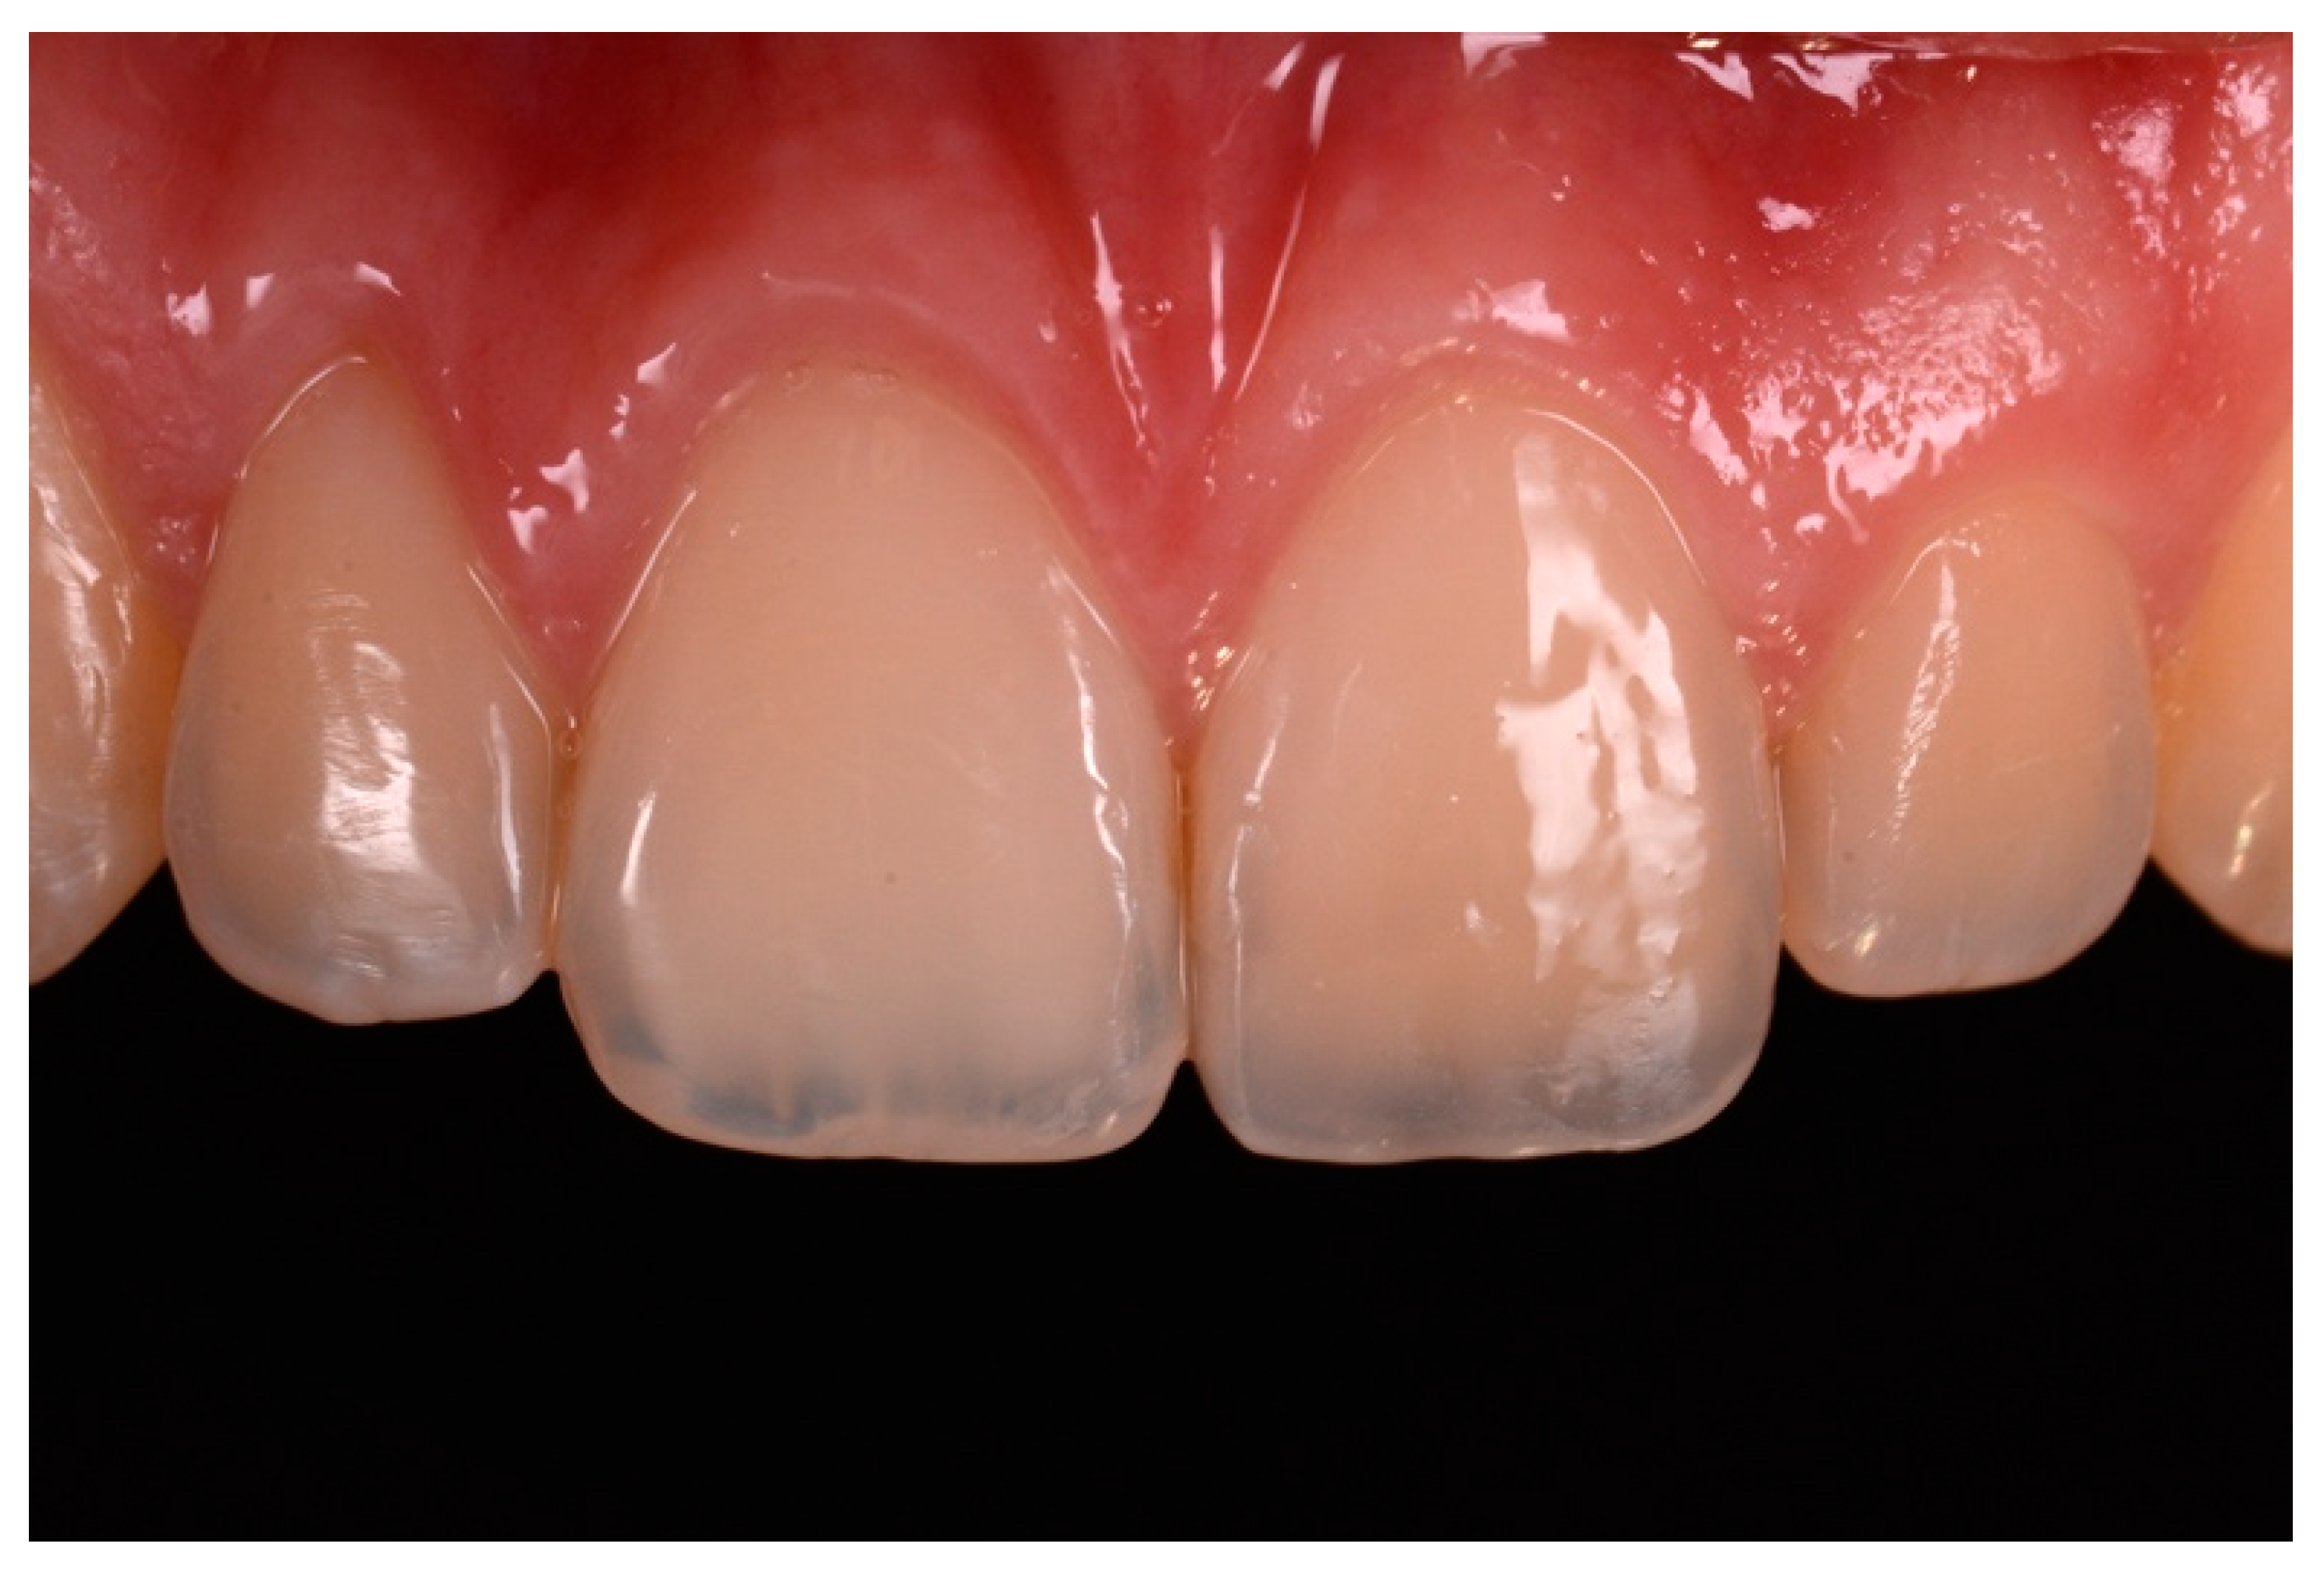

A healthy 23-year-old man referred to the dental office for the esthetic rehabilitation of right central maxillary incisor (Figure 48). Shade was selected as described in previous cases, using the button-try technique [14]. After isolation, preparation (Figure 49) and adhesive procedures (Prime & Bond Active, Dentsply Sirona, York, PA, USA), the frame was completed (Figure 50, Figure 51 and Figure 52) using a silicone index prepared upon a wax-up using translucent and opaque materials (Ceram.x Spectra Effects D1, E1, A1, Dentsply Sirona, York, PA, USA).

Excesses were removed from the frame (Figure 53) and silane and adhesive were applied following the step-by-step procedure described in Section 2.1.2. Dentinal body (Ceram.x Spectra Effects D1, Dentsply Sirona, York, PA, USA) (Figure 54) was applied to reproduce internal anatomy and then the external translucent enamel and body (Ceram.x Spectra Effects E1, A1, Dentsply Sirona, York, PA, USA) were applied checking precisely thickness and removing excesses with a caliper (Figure 55 and Figure 56) (TNCALIBRA, HuFriedy, Chicago, IL, USA). The restoration shows good integration one-year post-operative (Figure 57).

Figure 57.

One-year post-operative.